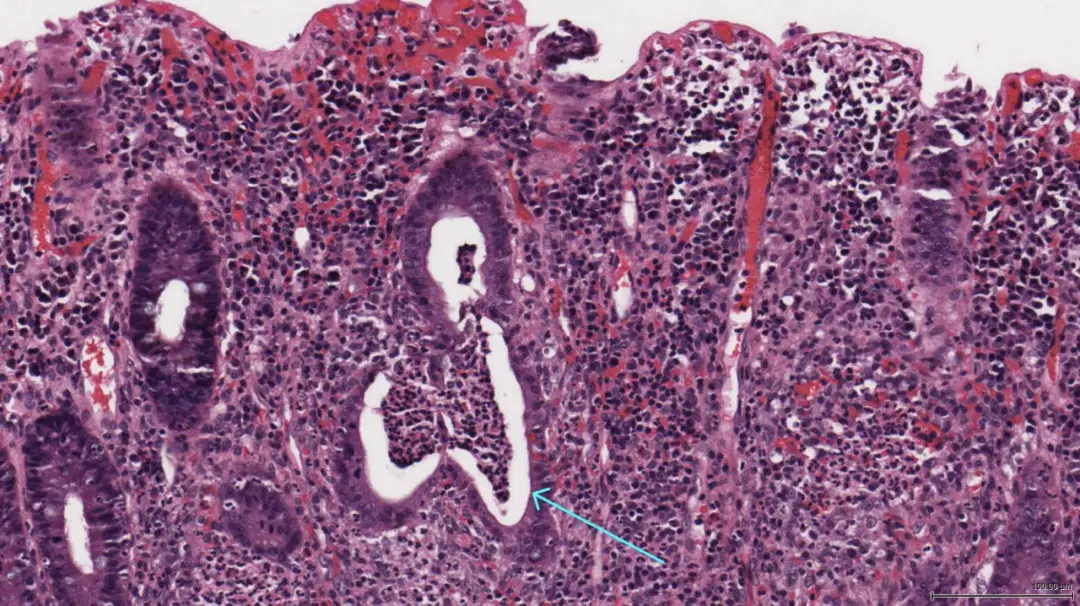

医生说,克罗恩病是一种炎症性肠病,那条线样征就是肠道炎症的表现。听起来挺专业的,但我只知道自己每次肚子疼得死去活来,那种感觉真的太难受了。吃不下饭,睡不好觉,甚至连笑都觉得费劲。那条线,就像是在嘲笑我,看你还能撑多久。